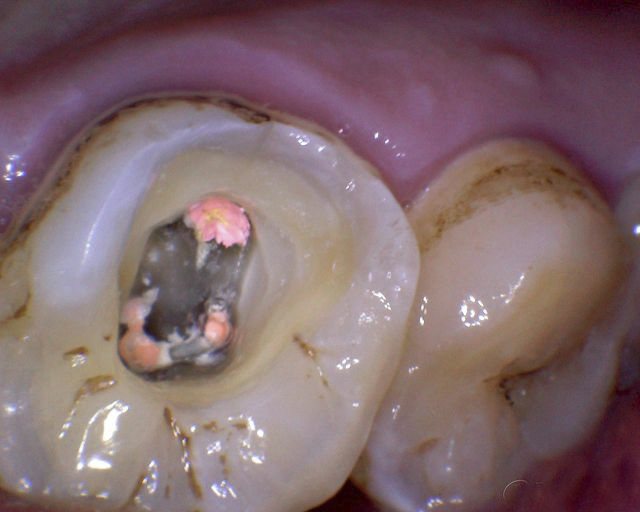

牙髓炎圖片